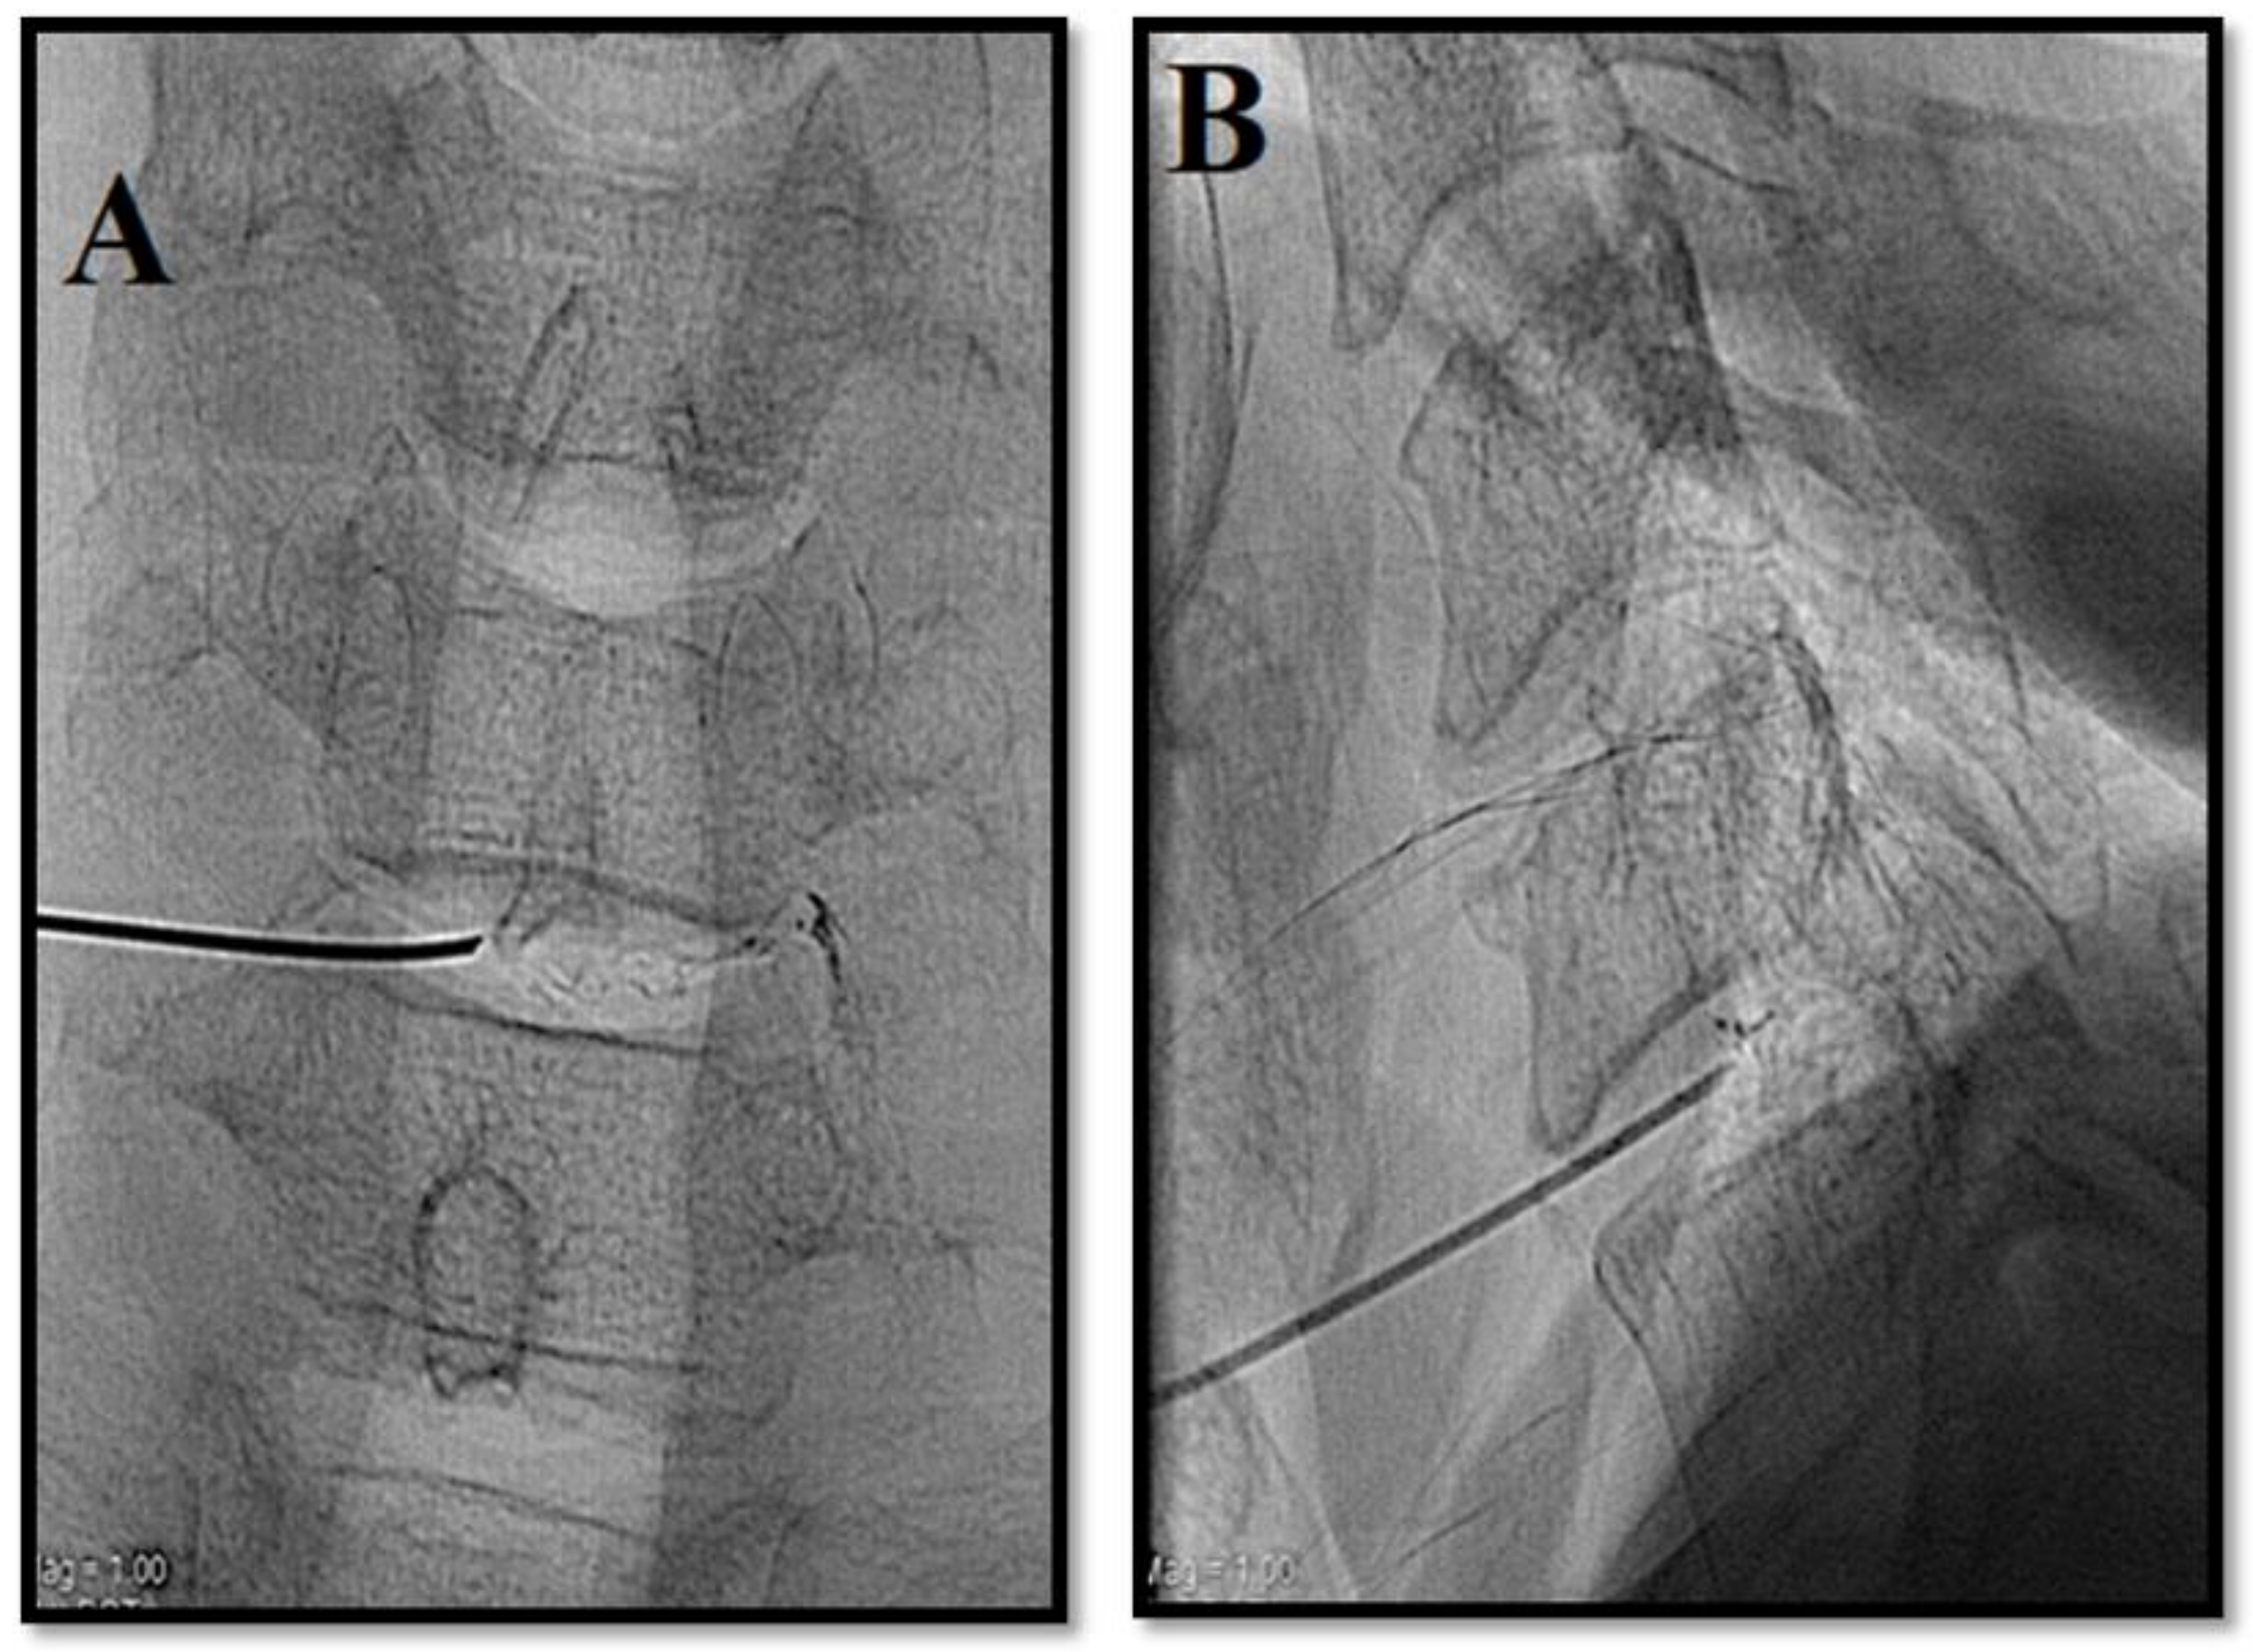

- Muto, M.; Andreula, C.; Leonardi, M. Treatment of herniated lumbar disc by intradiscal and intraforaminal oxygen-ozone (O2-O3) injection. J. Neuroradiol. 2004, 31, 183–189. [Google Scholar] [CrossRef]

- Ezeldin, M.; Leonardi, M.; Princiotta, C.; Dall’Olio, M.; Tharwat, M.; Zaki, M.; Abdel-Wanis, M.E.; Cirillo, L. Percutaneous ozone nucleolysis for lumbar disc herniation. Neuroradiology 2018, 60, 1231–1241. [Google Scholar] [CrossRef]

- Giurazza, F.; Guarnieri, G.; Murphy, K.J.; Muto, M. Intradiscal O2O3, rationale, injection technique, short- and long-term outcomes for the treatment of low back pain due to disc herniation. Can. Assoc. Radiol. J. 2017, 68, 171–177. [Google Scholar] [CrossRef]

- Ozcan, S.; Muz, A.; YildizAltun, A.; Onal, S.A. Intradiscal ozone therapy for lumbar disc herniation. Cell Mol. Biol. (Noisy le Grand) 2018, 64, 52–55. [Google Scholar] [CrossRef]

- Murphy, K.; Elias, G.; Steppan, J.; Boxley, C.; Balagurunathan, K.; Victor, X.; Meaders, T.; Muto, M. Percutaneous treatment of herniated lumbar discs with ozone: Investigation of the mechanisms of action. J. Vasc. Interv. Radiol. 2016, 27, 1242–1250. [Google Scholar] [CrossRef]

- Niu, T.; Lv, C.; Yi, G.; Tang, H.; Gong, C.; Niu, S. therapeutic effect of medical ozone on lumbar disc herniation. Med. Sci. Monit. 2018, 24, 1962–1969. [Google Scholar] [CrossRef]

- Zhang, Y.; Ma, Y.; Jiang, J.; Ding, T.; Wang, J. Treatment of the lumbar disc herniation with intradiscal and intraforaminal injection of oxygen-ozone. J. Back Musculoskelet. Rehabil. 2013, 26, 317–322. [Google Scholar] [CrossRef]